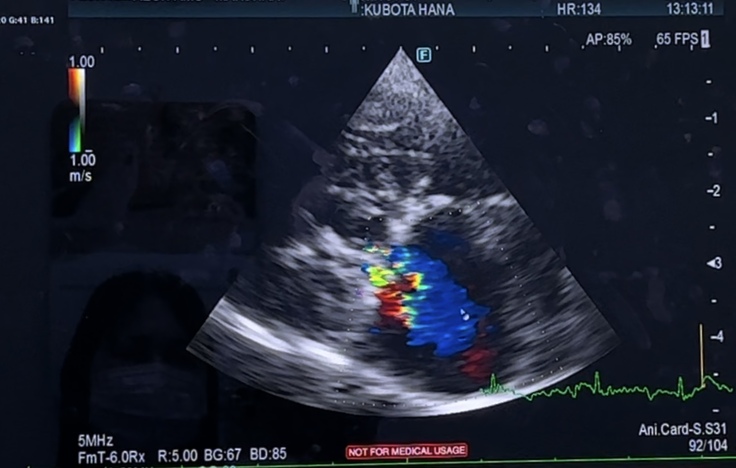

まず、心臓に関しては

逆流が残っている箇所も、大きさも

良くも悪くも、変わらず…

三尖弁の逆流、肺高血圧症も

悪化はなく、中等度でした